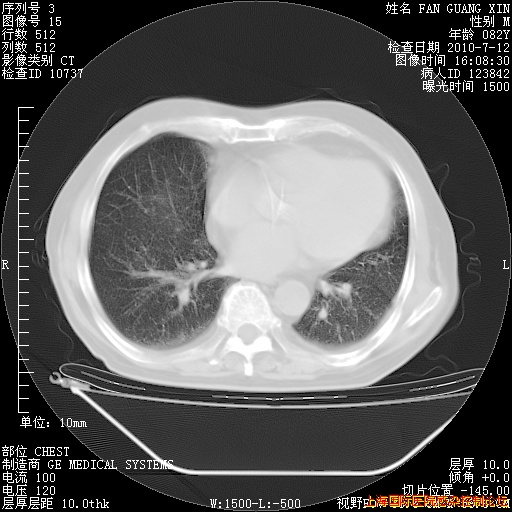

补发6月12日肺部CT肺窗

6月12日肺窗